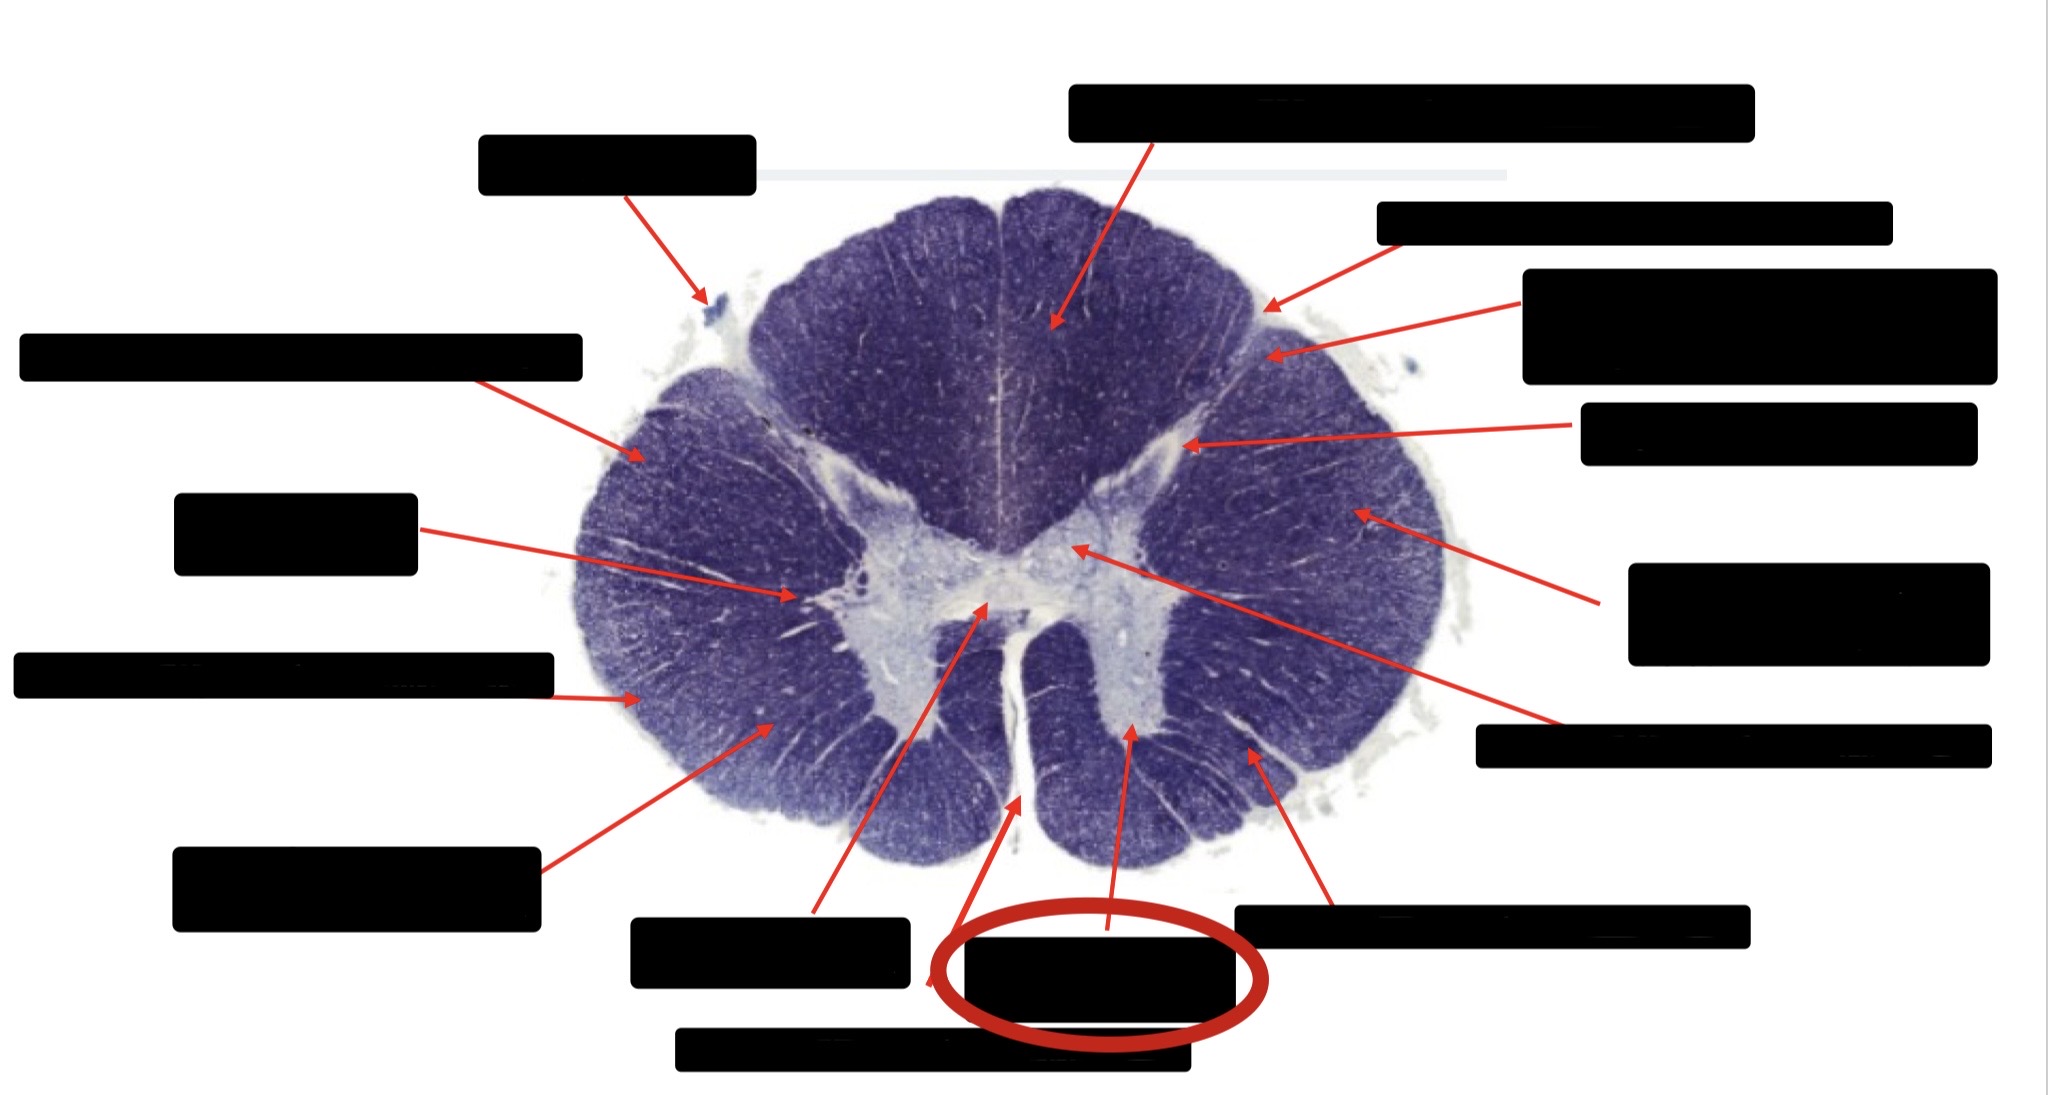

Dorsal Rootlet

Posterior Spinocerebellar Tract

Lateral Corticospinal Tract

Anterior Spinocerebellar Tract

Spinothalmic Tract

Central Canal

Anterior Corticospinal Tract

Posterior Column (Fasciculus Gracilis)

Posterior Column (Fasciculus Cuneatus)

Substantia Gelatinosa

Accessory Nerve Fibers

Anterior Horn Motor Fibers (Accessory Muscles)

Anterior Horn Motor Fibers (Proximal Muscles)

Ventral Root Fibers

Anterior Horn Motors Neurons (Proximal Muscles)